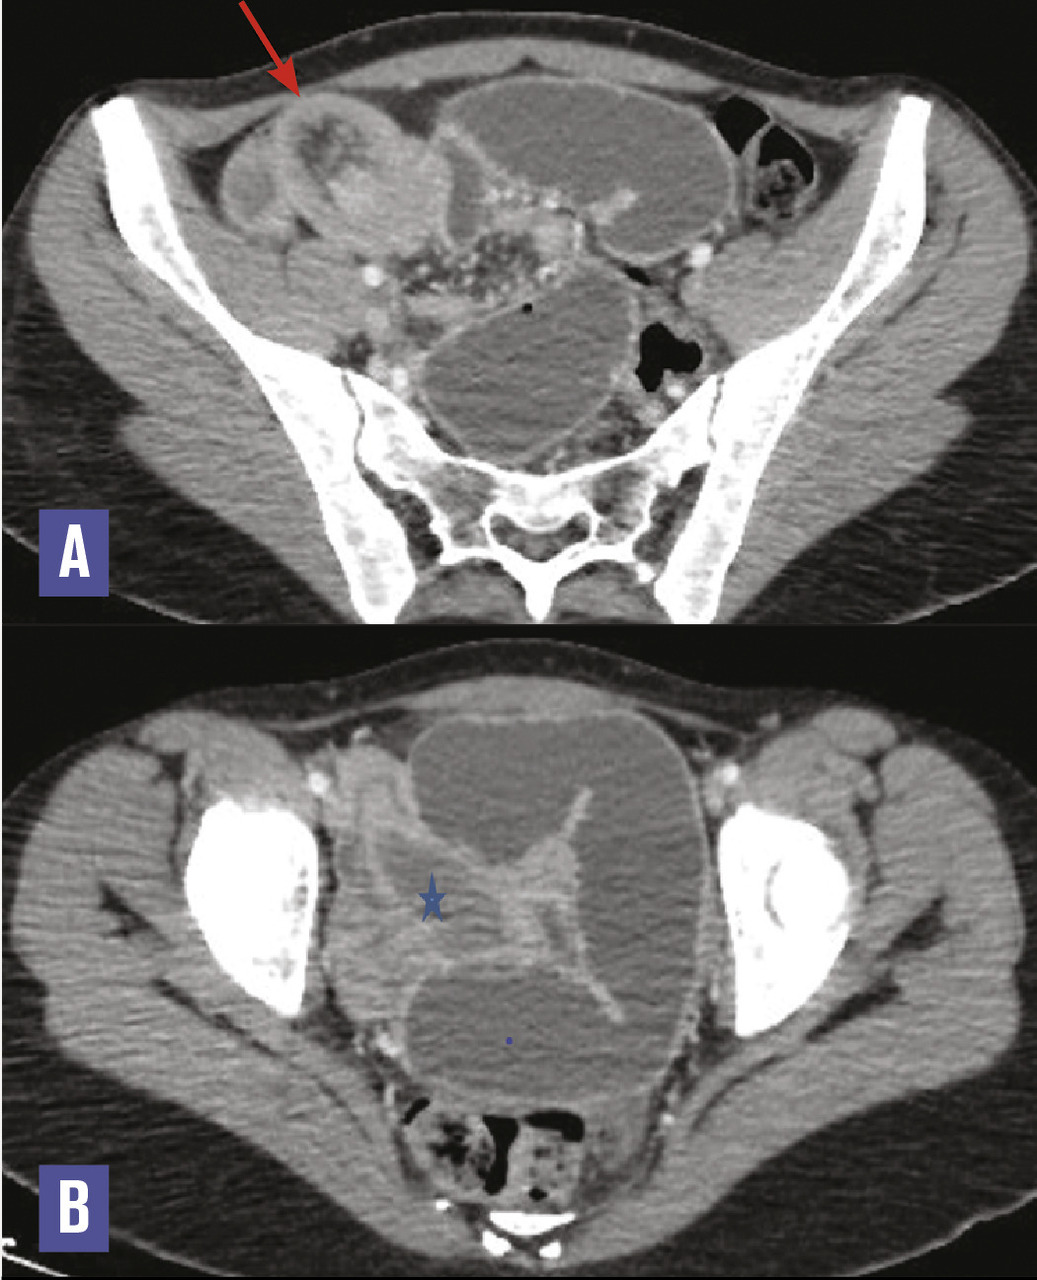

Cette femme de 19 ans consultait pour des douleurs abdominales diffuses et des vomissements post-prandiaux tardifs. Elle signalait des douleurs récurrentes et un arrêt des matières et des gaz. À l’examen, l’abdomen était distendu, avec un tympanisme à la percussion signant l’occlusion intestinale. Le bilan biologique était normal. L’échographie abdominale montrait une image d’invagination grêlo-grélique au niveau du pelvis. La tomodensitométrie confirmait l’invagination intestinale (fig. 1A ), avec à son pied une lésion ovalaire, bien limitée, hypodense, rehaussée faiblement et en périphérie après contraste (fig. 1B ). L’exploration chirurgicale trouvait une invagination iléo-iléale secondaire à une formation polyploïde intraluminale sessile ; l’anse invaginée était réséquée et la continuité rétablie par une anastomose grêlo-grélique termino-terminale. La pièce de résection de 21 cm renfermait un polype sessile de 40 x 20 x 20 mm avec, à l’examen histopathologique, un polype fibroïde inflammatoire (fig. 2 ). Les suites postopératoires étaient simples sur un recul de 3 mois.